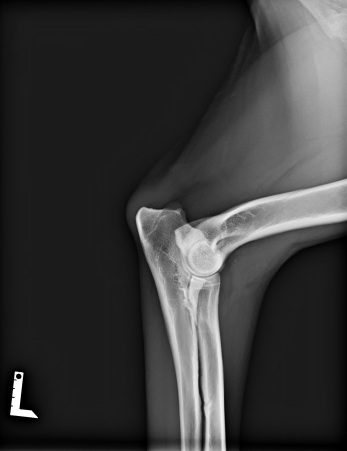

Radiographie d'un coude gauche d'un AS

L'analyse des radiographies permet de classer la dysplasie en 4 stades, de 0 (absence totale de dysplasie) à 3 (dysplasie sévère), en passant par les stades 1 et 2.